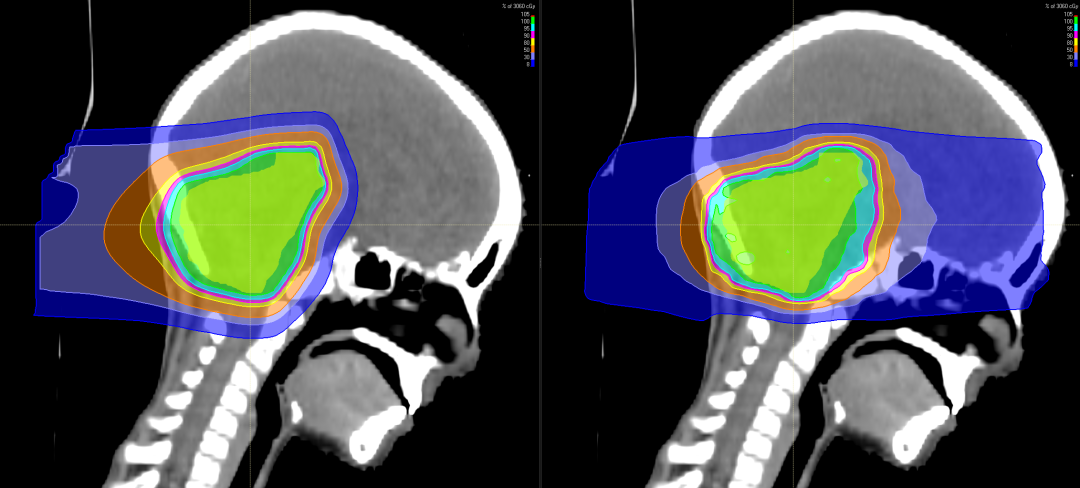

有研究表明,儿童神经母细胞瘤使用质子治疗的最大效益在于减少脑部正常组织构造的损伤,进而降低长期伤害。质子治疗是一种比其他任何形式的放射治疗更准确,更精确地靶向肿瘤,同时保留健康组织,目前全球最先进的一种放疗技术。通过质子治疗,可以最大限度地避免靶标外部的绝大多数不必要的辐射。

与传统形式的辐射相比,质子束会到达肿瘤内部的精准位置而不是沿着光束离开人体的路径释放大部分辐射剂量。实际上,质子没有肿瘤之外的辐射“退出剂量”,这意味着质子停在肿瘤上,不会继续伤害身体的健康部位。

对肿瘤周围组织损伤小不影响生长发育

随着儿童癌症治疗进步,儿童的存活率上升,存活下来的儿童患者日后之生活品质越来越受到关注,质子治疗具备能够减少散射剂量的优势,提升对肿瘤局部的控制,同时由于脑部神经组织多,易受辐射损害。质子治疗因具有布拉格峰的物理特性,使峰值部位对准肿瘤病灶处,发出最高剂量,产生最高峰,达到最佳杀瘤效果;峰后剂量趋于零,对周边脑组织几乎无影响。对于儿童脑瘤,可以避免有常规化疗引起的听力丧失、认知功能障碍、智力影响等。